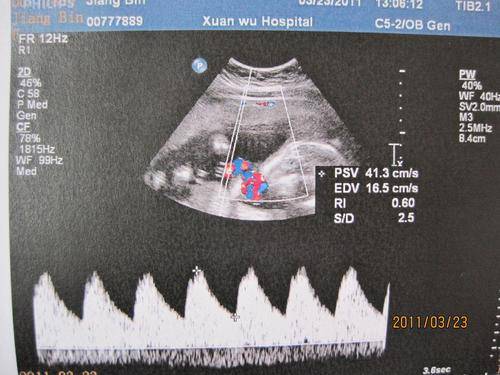

2.若是从B超数据中来分辨胎儿的性别,便是非常不准确,也没有科学依据的,因此B超辨别是根据显示屏看出,主要是以胎儿生殖器官来区分。

胎儿在20周的时候是可以通过四维彩超排查畸形的,但对于唇腭裂等最好是在怀孕22周-26周左右排查畸形,这是因为胎儿在这个时候发育非常迅速,胎儿的结构也完全发育,并且也能看出胎儿的大小、羊水适中,还有胎儿的在宫内的活动量及胎儿骨骼回声等,都显示的非常清晰。因此不能太早去排查胎儿畸形,以免只能看出大概,无法完全排查胎儿是否畸形。